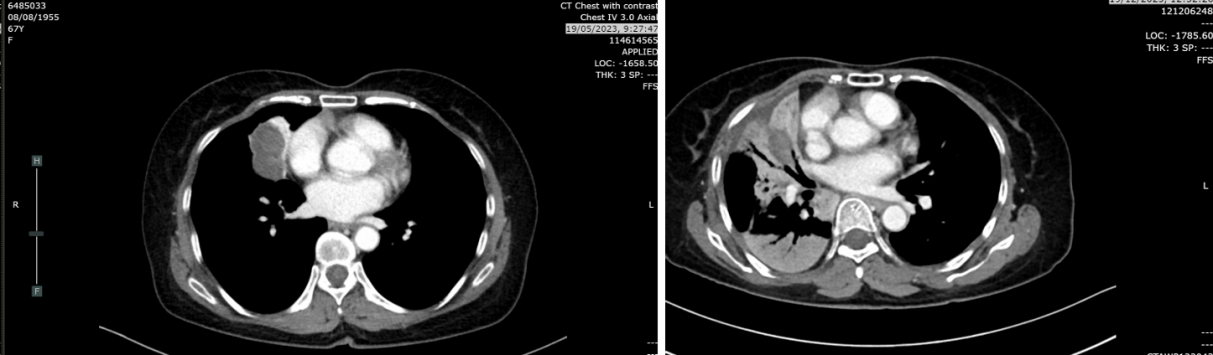

复查CT(2023-12-19):CT示肿块轻度增大至4.1cm(较7月增长24%),右肺上、中、下叶新见牵拉性支气管扩张及实变影,鉴别诊断包括浸润性转移、感染或混合性肺不张/实变。无肝、肾上腺、淋巴结或骨转移。

2024年3月21日:肿块缩小至2.8cm,实变及结节较前减少,考虑肺转移灶部分消退。

2024年6月17日:肿块略增至2.9cm,亚厘米级淋巴结。

2025年8月26日:肿块2.2cm,右肺上叶、中叶结节0.3-0.4cm稳定,中叶新增磨玻璃影(考虑感染或炎症),无新增转移灶。

疗效总结:自治疗开始计算,无进展生存期(PFS)达186周(3.5年);自停药后计算,PFS为102周(2年)。